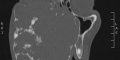

La massa tumorale è stata rimossa dopo un lunghissimo intervento eseguito dall’equipe medica guidata dalla professoressa Adriana Cordova e il professore Francesco Moschella nel reparto di Chirurgia plastica.